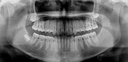

Introducing the CS 9300 Premium Panoramic, Cephalometric, and Cone Beam System from Carestream Dental – your ultimate solution for top-quality dental imaging. This state-of-the-art machine offers both 2D panoramic and cephalometric dental X-rays, as well as adjustable 3D cone beam images in up to seven different field of view sizes, extending up to 17x13.5 cm. This comprehensive range of imaging capabilities makes it a versatile tool, perfect for supporting a wide array of dental, surgical, or orthodontic examinations.

With the CS 9300 Premium, you can expect unparalleled image clarity and precision, allowing you to confidently diagnose and plan treatments with ease. Whether you're performing routine dental check-ups, complex surgical procedures, or orthodontic assessments, this system ensures outstanding results.

The CS 9300 is a multimodality imaging system that offers a wide range of 2D and 3D imaging options.

The CS 9300's 2D panoramic x-ray imaging capabilities are powered by variable focal trough technology, which provides optimal clarity for every image. The system's 3D imaging capabilities are based on cone beam technology, which delivers high-resolution images with a low radiation dose.